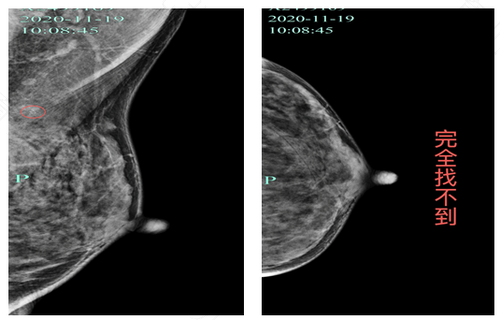

如果女性在检查中发现乳腺囊壁钙化,就必须要予以重视,要做一次全面的检查,例如乳腺b超,在必要的时候,还要进行病理分析,这就可以确认乳腺囊壁钙化是良性的还是恶性的。如果真的是恶性的,就必须要及时的治疗。